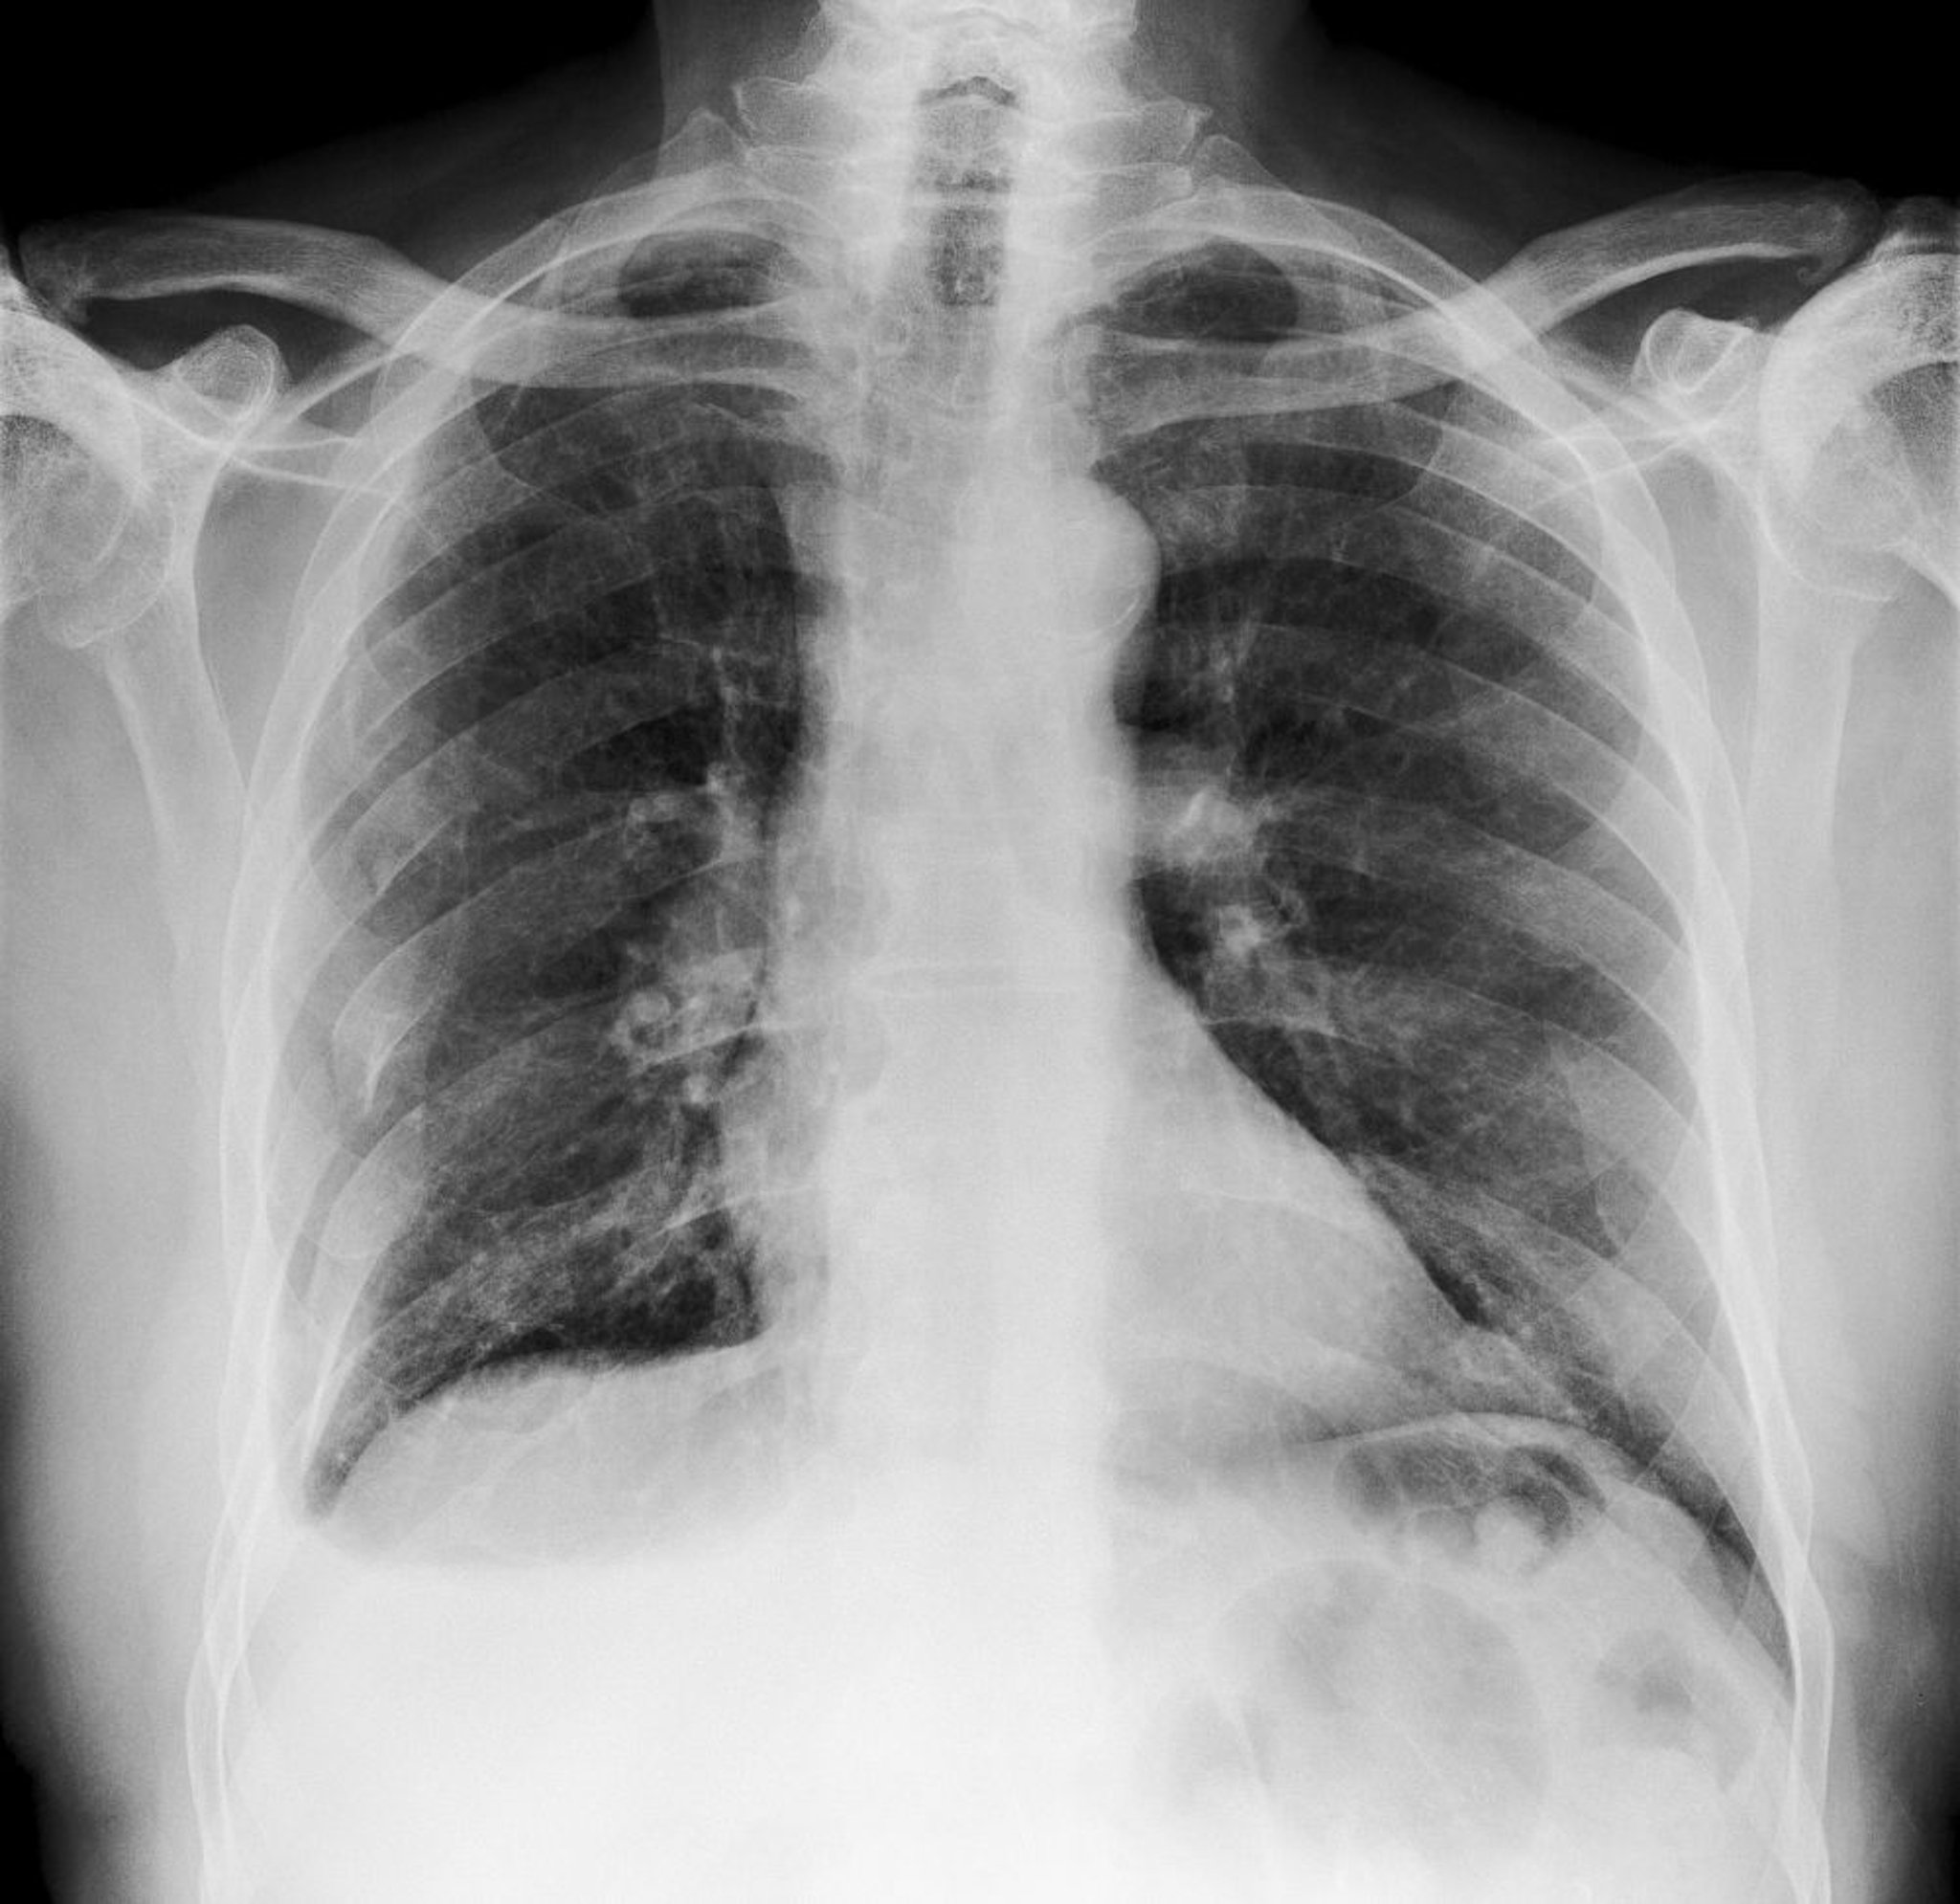

Diagnosi della frattura costale

• Di solito RX torace

La palpazione della parete toracica può identificare alcune fratture costali. Alcuni medici ritengono che l'anamnesi e l'esame obiettivo siano appropriati nei pazienti sani con traumi minori. Tuttavia, nei pazienti con trauma contusivo significativo, viene solitamente eseguita una radiografia del torace per verificare la presenza di lesioni concomitanti (p. es., pneumotorace, contusione polmonare). Molte fratture costali non sono visibili alla RX torace; specifiche proiezioni per coste possono essere fatte ma identificare tutte le fratture costali alla RX non è di solito necessario. Altri test diagnostici, come la TC, vengono eseguiti per verificare la presenza di lesioni concomitanti clinicamente sospette.